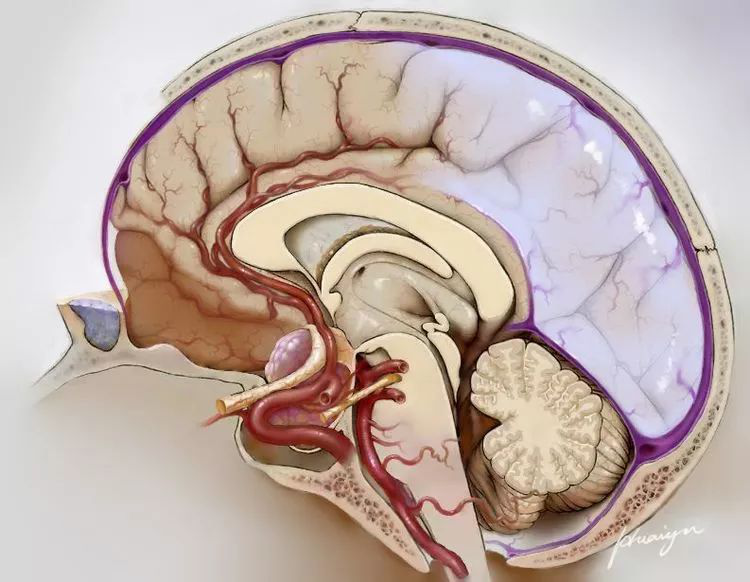

在矢状位上,于胼胝体膝部最前端做一水平线,此线以下之前额纵裂范围均属额底纵裂区域,后界即为终板。相较纵裂的其他区域或侧裂来说,此区域的特征十分显著:由前向后两侧额极连接极为紧密,无池且深狭,其间有双侧大脑前动脉之 A2 段穿行(见下图)。

为了使将此区域做为路径以达至鞍区—下丘脑—三脑室的术者,更便于领悟理解和易于掌握此类手术,我又将之前已定义的“额底纵裂区域”再行深度解析,进一步划分出三个分区:

首先,以双侧大脑前动脉之 A2 段为界,其之前区域即是“额底纵裂区域前区”,其之后区域至终板止即是“额底纵裂区域后区”;

其次,额底纵裂投射于前颅凹底和鞍区中线的相应区域可称之为 “额底纵裂区域底区”。

下面将此三个分区详述如下:

1、额底纵裂区域前区

双侧大脑前动脉 A2 段之前的额底纵裂区域即为前区(见下图)此区之特点是,约占额底纵裂区域的 90%。多数情况下,此区之双侧额叶沟回呈犬牙交错状紧密相贴致蛛网膜紧紧相连,少有缝隙而无蛛网膜池状结构。因之,无创伤的分开此区,有时会变得异常艰难而费时。非极具耐心定力锐性分离而不能。此区分离是经额底纵裂区域手术的关键步骤,不仅耗时,而且若在分离过程中,对双侧额叶皮层及其表面静脉的损伤过重过多时,就会使双侧前额内侧纵裂区的水肿加重,极端重度水肿甚至可引发致命的“中央型脑疝”。

2、额底纵裂区域后区

此区位于双侧大脑前动脉A2段的后部止于终板(见下图)与前区相比,后区所占空间小且两侧皮层少有粘连,蛛网膜较为疏松易于分离。但由前区进入到后区尚存有一扇“大门”,此“门”由位于两区之间的双侧大脑前动脉之 A2 段构成,它是前后区相互联通进入终板前的必经之“门”,亦是此路径上的最后障碍。由于,双侧 A2 段经常呈“拧麻花” 状紧密粘连而致“大门”紧闭,所以,小心细致地进行锐性分离,从而将 A2 段完全分开,是最大程度打开此“门”的关键环节。当“大门”彻底打开(向两侧分别牵拉 A2 段)后,由于后区路径已不存阻碍,终板遂能充分显露,终板路径得以打通。有时,因肿瘤巨大并突向前方生长,后区亦会消失。

3、额底纵裂区域底区

额底纵裂投射在相应的前颅凹底和鞍区中线的区域均可归入此区内,其所涉结构较多(见下图)。此区在前颅凹底中线区的宽度,根据解剖特征和与手术关联的程度,可划分为:本区的两侧外缘是以前床突外缘至筛板外侧缘的连线为界,此连线可由前床突再向后延,经视神经至视交叉止;本区之后缘为视交叉之后缘或前交通动脉;前缘可至鸡冠水平。由是观之,本区内的结构由前向后计有:鸡冠、筛板、蝶骨平台、鞍结节、前床突、视神经、蝶鞍、视交叉和前交通动脉。常常提到的视交叉池通路即在底区内。

以上述及了“额底纵裂区域”的三个分区结构特征。其实,通过额底纵裂区域路径切除累及鞍区—下丘脑— 三脑室内之区域的肿瘤,主要就是利用了两条通路,即位于额底纵裂区域底区的视交叉池通路和位于额底纵裂区域后区的终板通路。这两个通路可根据术中需要予以扩展:将视交叉向前牵拉(无涉前交通动脉)可扩大终板间隙,这样可更好地处理鞍上区的肿瘤;亦可通过磨除鞍结节,甚或部分蝶骨平台,以扩大视交叉池间隙,可彻底切除侵入到鞍内的肿瘤组织。